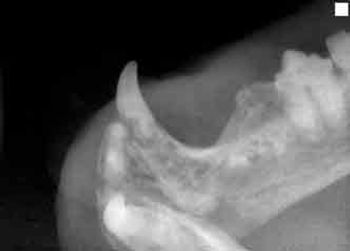

Tooth resorption is the most common dental problem in cats, with studies worldwide showing a prevalence rate (in cats presented for dental problems) of up to 75%.